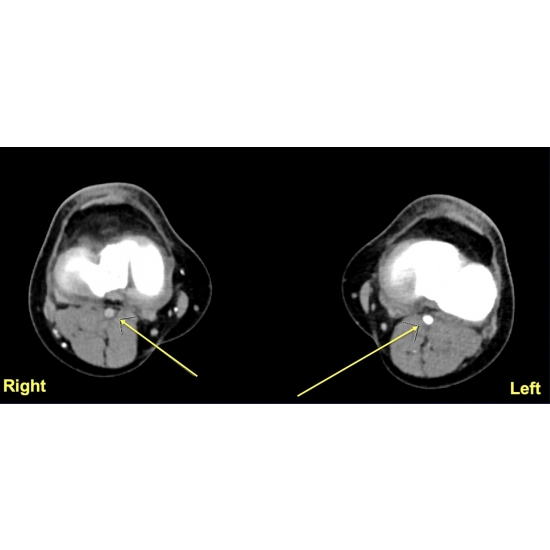

| Poor Perfusion Or Elevated Pressures? An Exertional Lower Limb Pain Conundrum - Page #3 | |||